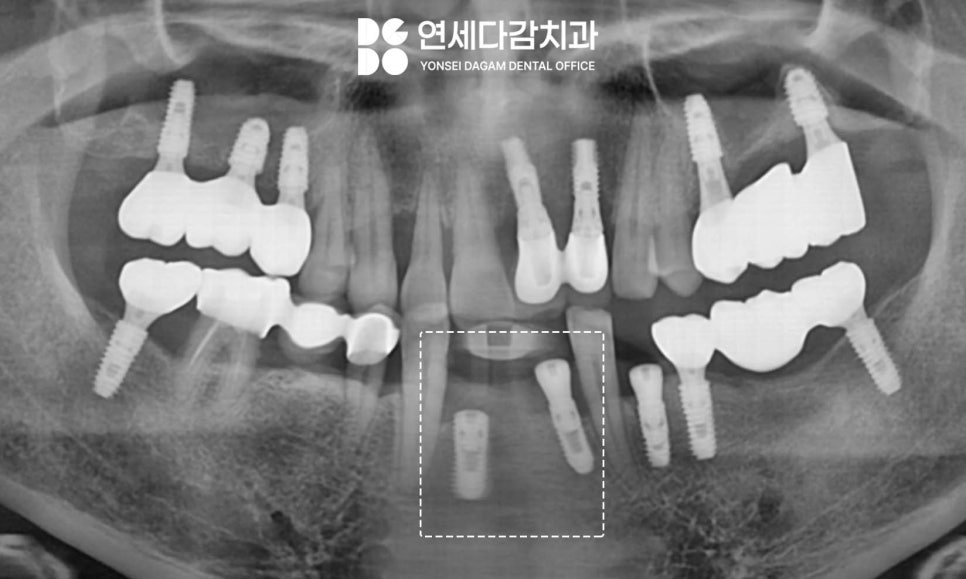

이 과정을 통해 수술 부위 모두

골 유착이 원활하게 진행되어

안정적인 결과를 얻을 수 있게 됩니다.

임플란트 표면 처리 기술의 발전으로

다양한 타입의 제품이 개발되어

선택지가 많아졌습니다.

임플란트 치료는 개개인의

뼈 상태와 구강 환경,

그리고 적절한 제품 적용이

모두 어우러질 때

이상적인 결과를 얻을 수 있습니다.